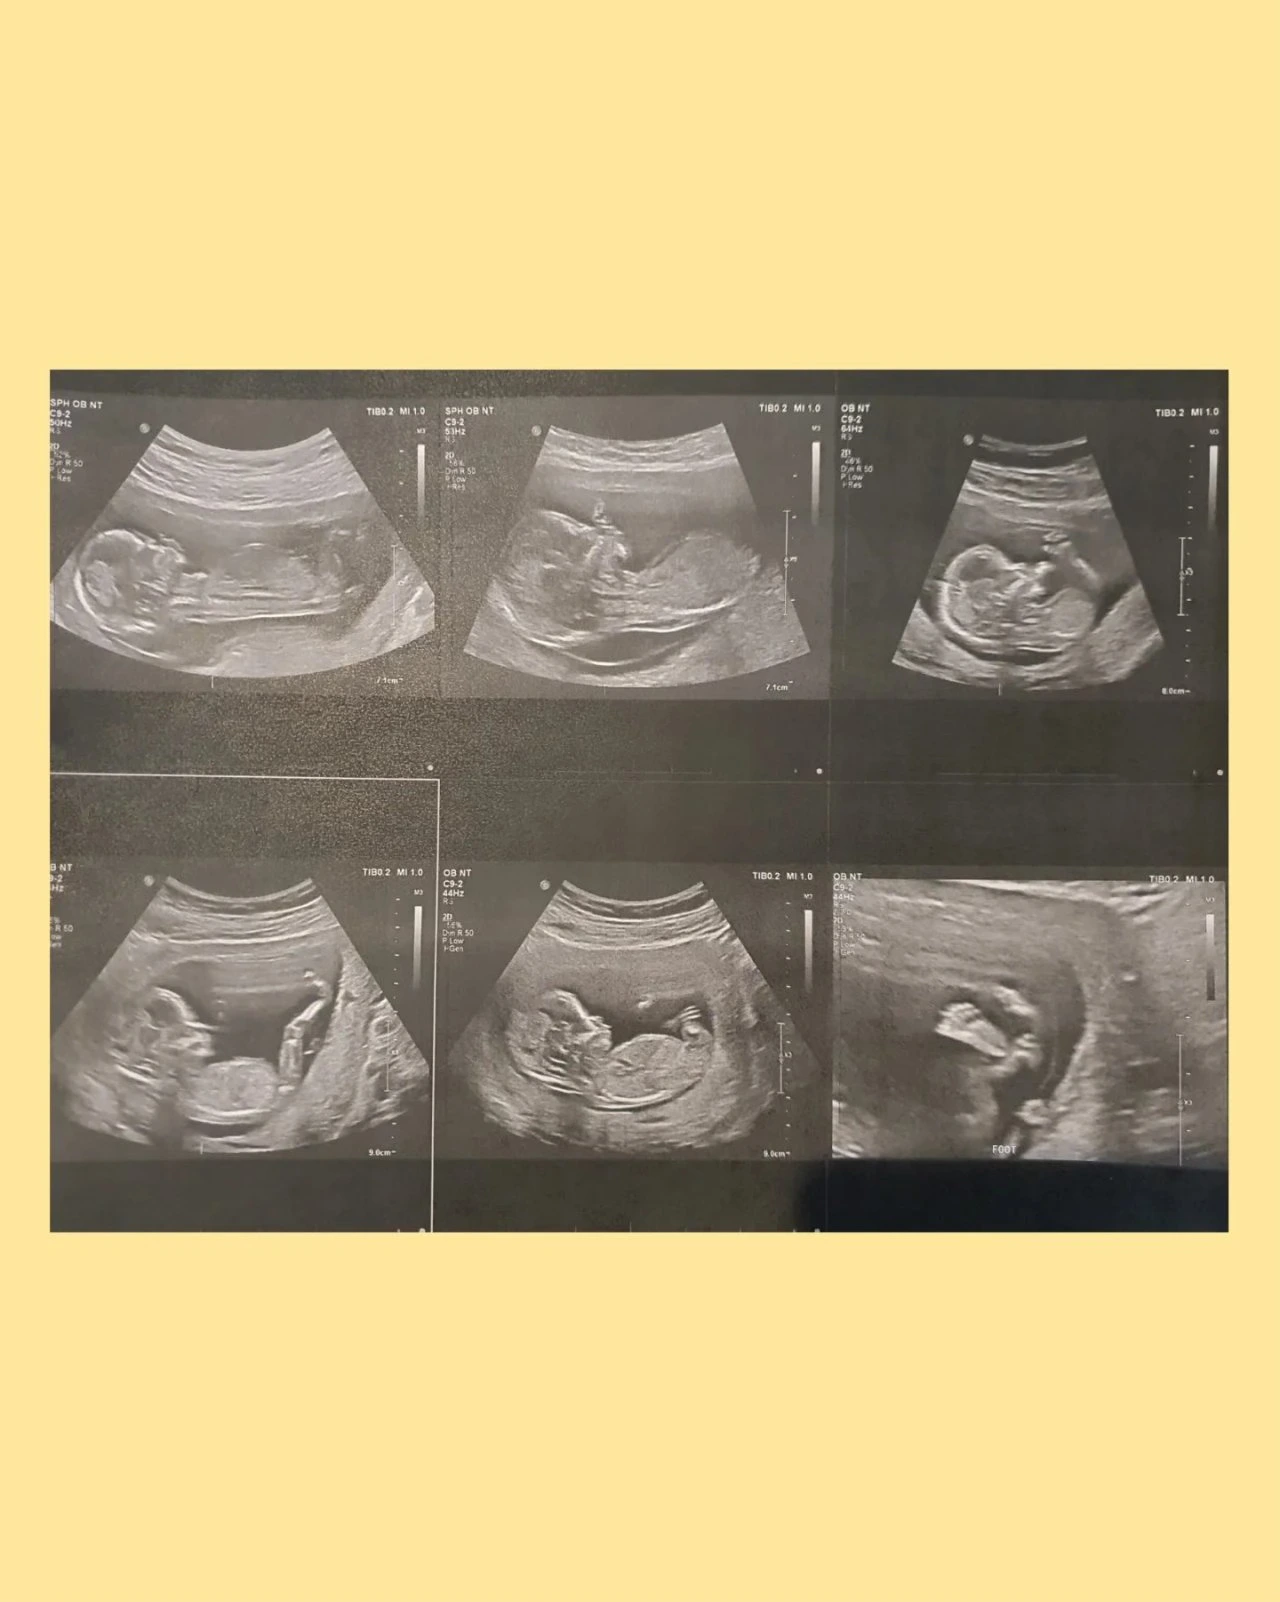

tempImageQjcxd0.heic

아기의 맥박소리를 들으니 무엇이 그렇게도 신비롭던지! 남편과 나는 눈물보다는 어마어마한 미소로 아기의 움직임과 건강한 신체를 살펴볼 수 있었고, 나도 모르게 ‘엄마에게로 와줘서 고마워’라고 조용히 속삭이고 있었다.